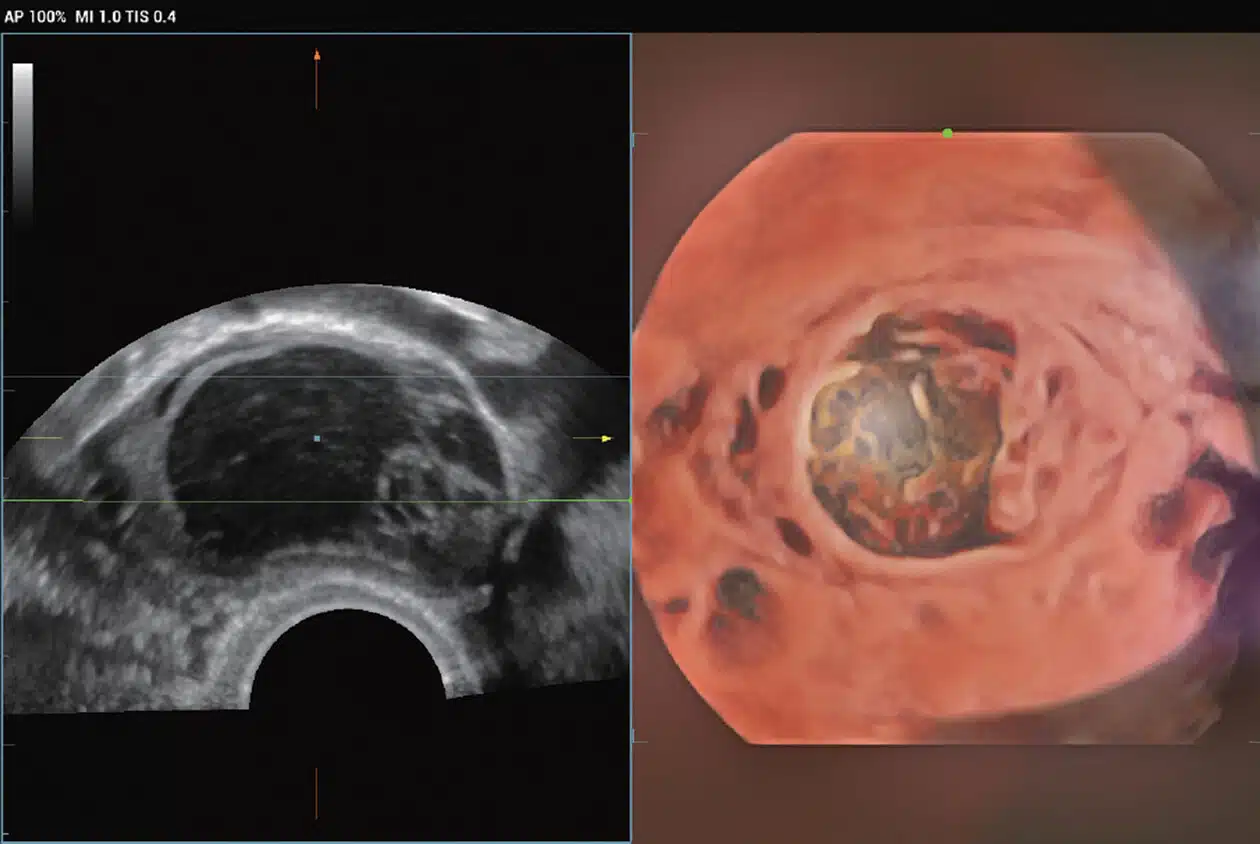

• Ovarian-tumor_Imagyn-I9.jpg

Ovarian Tumor

• Early-OB-fetus-with-iLive_Imagyn-I9.jpg

Early OB Fetus Displaying iLive with Hyaline